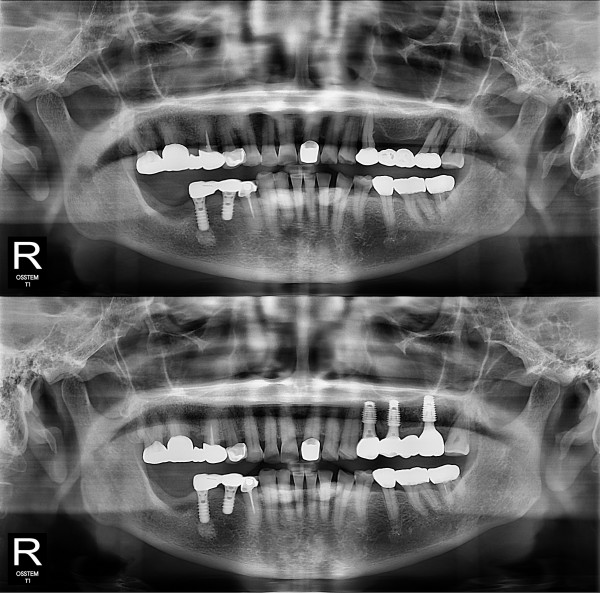

种植牙

局部种植牙